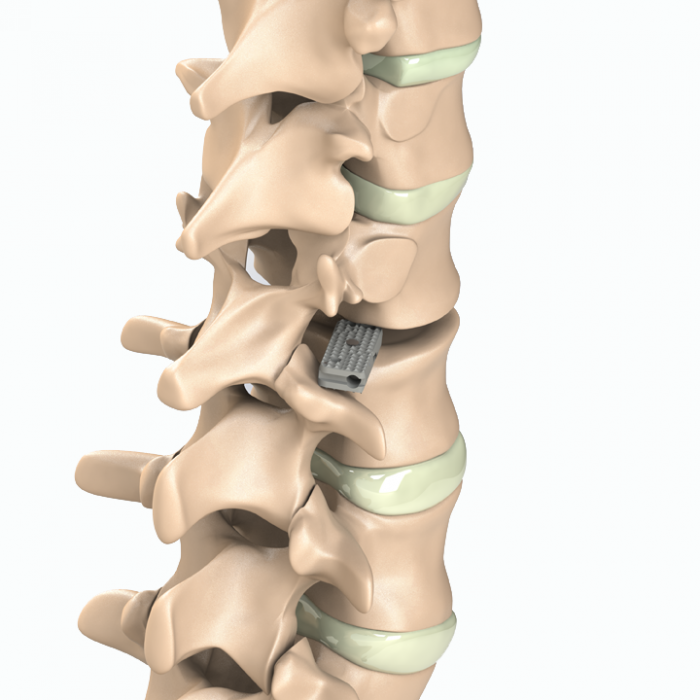

Aditus Lumbar Xlif Cage

- Easy to Place within Disc Distance and Thanks to Elliptical Front Design

- Applicability of Posterior, Posterior Lateral or Extra Lateral from Disc Distance

- Functionality Leverage from 5 Points for Axial Loading Simple Implantation